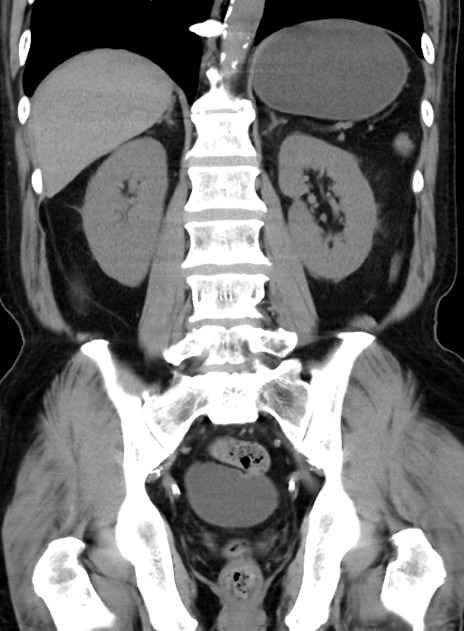

症例38(冠状断像)

【症例】70歳代 男性

【主訴】腹痛・嘔吐

【現病歴】昨晩より、嘔吐・腹痛あり。今朝になっても嘔吐あり。来院。

【既往歴】心臓バイパス手術、開腹胆摘、腸閉塞

【身体所見】BP 107/71mmHg、HR 116/min、腹部:平坦、軟、下腹部に軽度圧痛あり。反跳痛なし。

【データ】WBC 15100、CRP 0.32